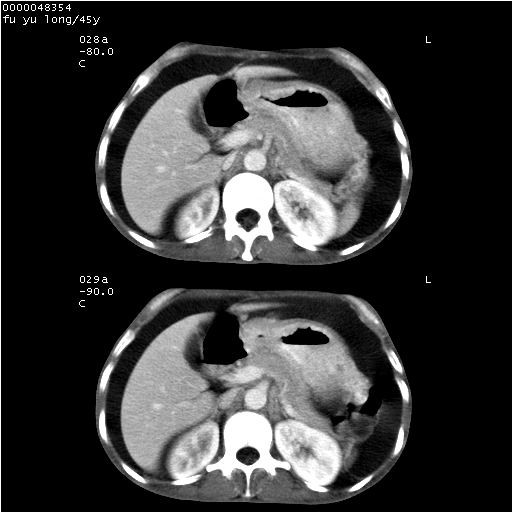

以下是引用lkc8963在2008-5-30 8:44:00的发言:[br]胃窦癌伴网膜(胃结肠韧带)/腹膜及腹膜后淋巴结转移.

以下是引用医影拾贝在2008-5-30 2:38:00的发言:[br]气肿性胃炎、胃十二指肠溃疡、腹膜炎,考虑穿孔可能性较大